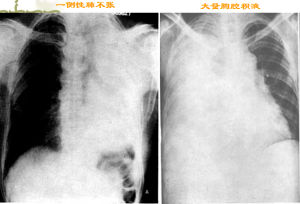

2. 如何判斷肺紋理是否正常?一側肺野從肺門到肺的外周分為三等份分別稱為肺的內、中、外帶,正常情況下肺內中帶有肺紋理,外帶無,如果外帶出現了肺紋理則有肺紋理的增多,反之內中帶透亮度增加則肺紋理減少。對肺內中外帶的區分還有一個意義,那就是對肺氣腫時肺壓縮的判斷,一般來說肺內中外帶占肺的量分別為60%、30%、10%。

我們知道一側肺野從肺門到肺的外周分為三等份分別稱為肺的內、中、外帶,正常情況下肺內中帶有肺紋理,外帶無,如果外帶出現了肺紋理則有肺紋理的增多,反之內中帶透亮度增加則肺紋理減少。對肺內中外帶的區分還有一個意義,那就是對肺氣腫時肺壓縮的判斷,一般來說肺內中外帶占肺的量分別為60%、30%、10%。縱膈與肺門